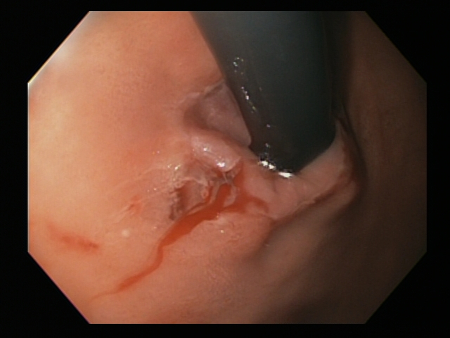

[Figure caption and citation for the preceding image starts]: Mallory Weiss tear after application of through-the-scope clip results in haemostasisFrom the personal collection of Douglas Adler; used with permission [Citation ends].